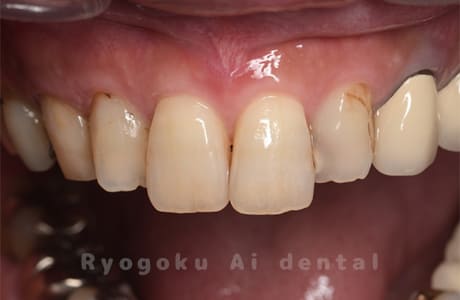

Case13

- 前歯部補綴不適合

- 治療内容

- 374,000円

前歯の形、色が気になるとのことでご来院された患者様です。前歯を白く仕上げてほしいとのことで、周りの歯よりも若干白く仕上げることとなりました。

<リスク・副作用>

過度の咬合や衝撃で割れることがあります。